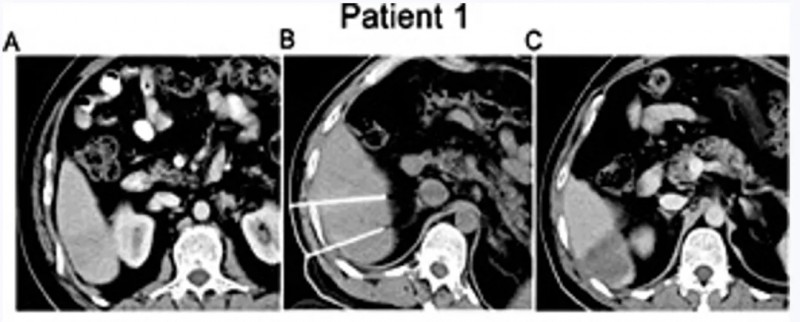

研究中两例IRE-NK组患者的疗效尤为突出,治疗3个月后经磁共振成像(MRI)评估均达到完全缓解(CR),具体情况如下:

患者1:男性,44岁,2016年4月确诊IV期肝细胞癌,初始HCC结节最大直径3.5cm(详见下图A)。IRE+同种异体NK细胞联合治疗后MRI显示:占位性病变无强化(详见下图C),病灶区域轻度萎缩。

▲图源“Cell Physiol Biochem”,版权归原作者所有,如无意中侵犯了知识产权,请联系我们删除

患者2:女性,52岁,2016年7月入住复大肿瘤医院,IV期肝细胞癌,初始HCC结节最大直径3.0cm(详见下图A)。IRE+同种异体NK细胞联合治疗后MRI显示:病灶内可见大面积坏死(详见下图C)。